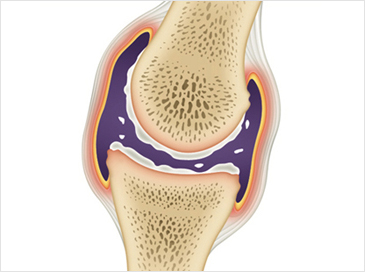

사람들이 나이가 들어감에 따라 자연적으로 관절이 안 좋아지는데요. 우리나라 성인의 만성질환 1위가 관절염이라고 하니 관절염으로 인한 통증으로 많이 불편해 하는 현실입니다. 관절염 통증은 많은 이유가 있겠지만 관절 사이에서 완충 작용을 하는 연골이 닳아서 충돌하면서 발생하는 경우가 많습니다. 이 연골의 주 성분이 콘드로이친 이라는 성분인데요.이 성분이 떨어지면 각종 관절염, 근육통 등 증상이 발생하게 됩니다. 콘드로이친은 우리 몸에서 스스로 생성되지 않는 성분으로 꼭 섭취를 통해서만 보충이 가능하다고 하네요.

최근에는 콘드로이친이라는 물질이 뜨고 있는데 그리스어로 연골이라는 의미의 콘드로이친은 상어와 소 연골에서 추출되는데 이는 관절끼리 부딪혀 마모되는 것을 막아주고 동시에 충격을 흡수하여 자유롭게 움직일 수 있도록 도와주어 건강 기능 식품으로 떠오르는 물질입니다.